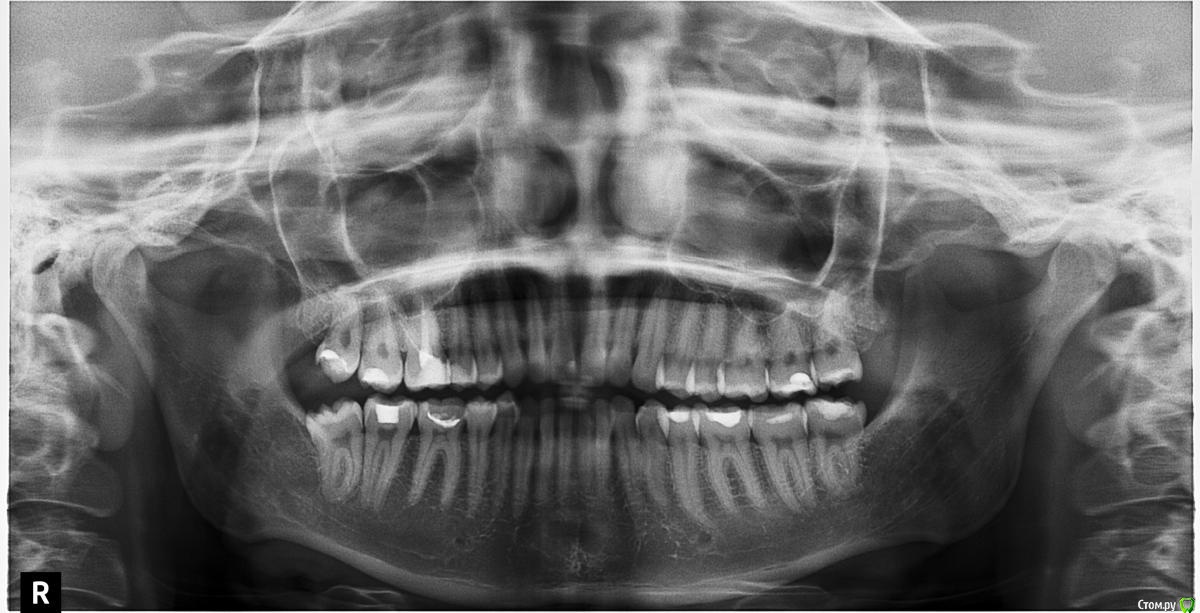

Альбинка Опубликовано 1 декабря, 2016 Поделиться Опубликовано 1 декабря, 2016 (изменено) Добрый вечер! У меня очень сильно портятся зубы (практически все пятерки, шестерки,семерки и восьмерки запломбированы), в сладком я себя ограничиваю, после еды полоскаю зубы, чищу два раза в день, проф.чистка два раза в год. Посоветуйте, пожалуйста, что нужно еще делать чтоб остановить этот процесс? и с чем связано такое состояние зубов? как предотвратить вторичный кариес? И еще, конкретный вопрос, насколько хорошо запломбирован канал 16 зуба? Как быть с чисткой межзубного пространством, нитка не пролезает, выход - купить ирригатор? Изменено 1 декабря, 2016 пользователем Альбинка Ссылка на комментарий

DmitrySH Опубликовано 1 декабря, 2016 Поделиться Опубликовано 1 декабря, 2016 И еще, конкретный вопрос, насколько хорошо запломбирован канал 16 зуба? Он беспокоит?Для ответа на вопрос минимум нужен прицельный снимок , но лучше КТ этого зуба Как быть с чисткой межзубного пространством, нитка не пролезаетВезде или только в каком-то месте? Ссылка на комментарий

Альбинка Опубликовано 2 декабря, 2016 Автор Поделиться Опубликовано 2 декабря, 2016 (изменено) Он беспокоит?Для ответа на вопрос минимум нужен прицельный снимок , но лучше КТ этого зуба Везде или только в каком-то месте? Он не болит, но присутствует некий дискомфорт, и еще он в целом потемнел Нитка везде не пролезает Изменено 2 декабря, 2016 пользователем Альбинка Ссылка на комментарий